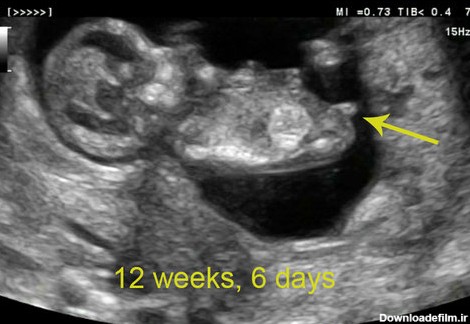

در عکس جنین در هفته دوازدهم بارداری اندام ها شکل گرفته و سر نسبت به بدن بسیار بزرگ است. تصویر جنین در هفته دوازدهم بارداری جنسیت جنین را مشخص نمی کند